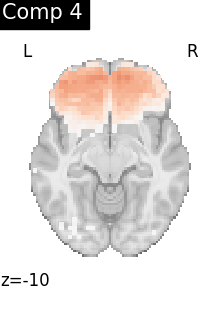

One plot of each component

for i, cur_img in enumerate(iter_img(dictlearning_components_img)):

plot_stat_map(

cur_img,

display_mode="z",

title=f"Comp {int(i)}",

cut_coords=1,

vmax=0.1,

vmin=-0.1,

colorbar=False,

)